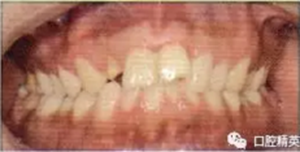

2冠根折,唇側(cè)斷端至齦下2mm,露髓,叩痛(+),不松,齦緣滲血;1冠折,未露髓,部分脫出,叩痛(+),松Ⅲ度,近中齦乳頭撕裂,長約1.5 cm;1挫入,切斷折斷,位于拉冠中部,叩診高調(diào)金屬音,不松,近中齦乳頭撕裂,長約1.5 cm;2見釉質(zhì)裂紋,叩痛(+),不松,齦緣滲血(圖1);以上牙齒X線均未見明顯根折線(圖2)。

圖1外傷即刻口內(nèi)像